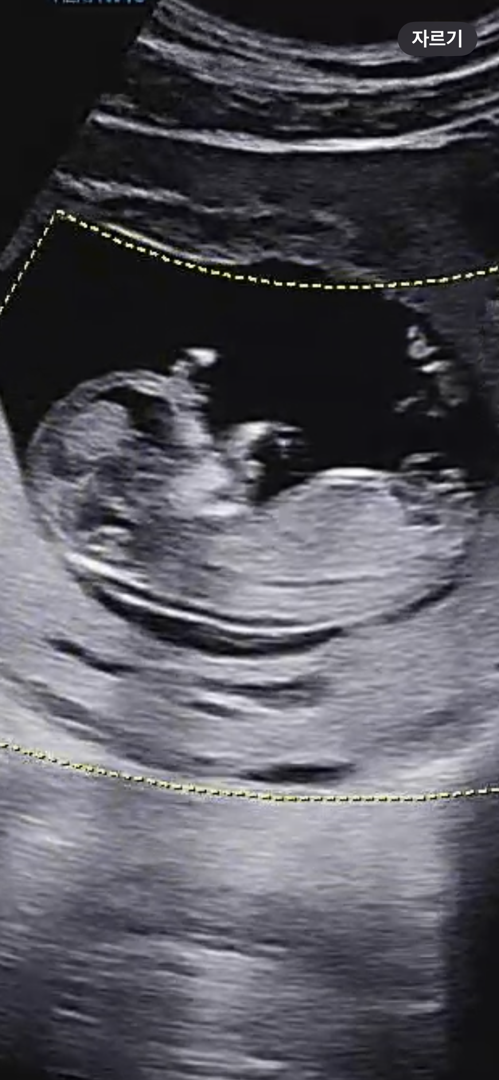

12주차 각도법 판독 부탁드립니다!

어디가 성기인지도 잘 모르겠는데 재미로 뵈주시면 감사하겠습니다.